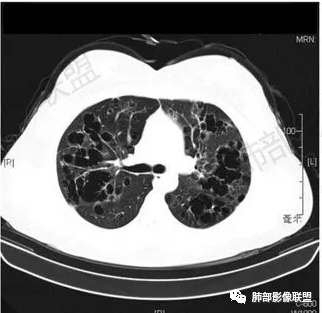

秦化君: 晨读 双肺不均匀散在多发囊状影,大小不等,部分囊形态欠规整,壁薄均匀,部分囊胸膜下平行。双肺少许斑片状磨玻璃影,边缘模糊。考虑BHD综合征。鉴别PCP,LIP。

红日初升: 中年女性,双肺多发气囊,背景干净,大小不一,下肺韧带旁较大,考虑BHD,鉴别LIP、LAM

宇宙: 中年女性,两肺多发大小不等薄壁囊状影,两肺纵膈胸膜下分布明显,考虑BHD,鉴别LAM

这个病例目前影像特点,多囊,囊主要位于下肺,胸膜下及小叶核心为主

伴随少许索条,而且这些病灶与囊不一定有相关性

囊的分布,PLCH基本可以排除

囊壁薄且均匀,光滑,形态规则,基本除外恶性

单纯囊,无斑片及其他实性病灶,感染不支持,可能的是:LAM、BHD、LIP

从囊的分布、大小,BHD可能性可能大一些,但是LIP、LAM都可以这样表现,具体诊断应该是这三种之一,影像缩小到这里我觉得就差不多了,结合临床考虑就行,不支持靠影像强下结论。

临床诊断BHD综合征需要满足一个主要或两个次要标准。主要标准包括:1、皮肤上至少发现5个纤维滤泡瘤,至少1个组织学证实;2、致病的FLCN种系突变阳性。次要标准:1、多发肺囊肿,双侧基底部,有或无自发性气胸;2、肾癌,起病早(<50岁)或多灶性或双侧;3、 BHD综合征一级亲属。BHD主要影像表现特征:1、两肺内肺囊肿:80%以上的BHD患者会出现肺内囊肿,且倾向于基底部近胸膜下分布,特别是纵隔侧肺膜下,囊肿形状不规则、囊肿可大可小,肺内囊肿多毗邻肺下动脉或静脉近端,胸部CT上囊肿分布和特点对诊断有提示意义。2、继发自发性气胸:BHD患者发生气胸风险是正常人的5倍,BHD患者的气胸发生率约为1/4,气胸复发率则高达59%。3、肾肿瘤:(常为双侧性、倾向于嫌色细胞组织学亚型)4、皮肤表现:(为面、颈部纤维性毛囊瘤、毛盘瘤)

PLCH通常发生在青年人,男性多见,与吸烟密切相关,患者可无症状或有呼吸困难;肺组织病理是朗格汉斯细胞增生及浸润为特征,形成双肺多发细支气管旁间质结节囊腔。

CT表现:早期阶段以结节为主,小结节分布于小叶内、支气管血管束旁及小叶间隔,囊腔形态不规则,呈分支状、两叶或三叶,大小不一,囊壁厚薄不均,主要以中上肺受累为主,双侧肋膈角往往不受累,终末期过度充气及广泛囊腔形成网状纤维化或终末肺气肿,也可导致自发性气胸。